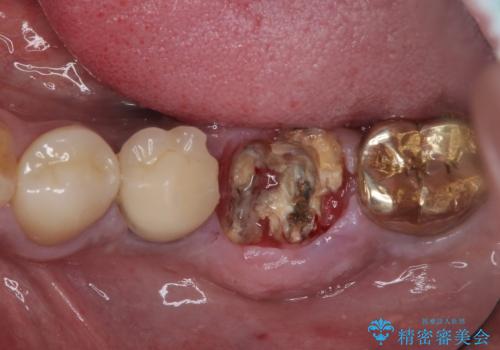

- 奥歯が割れてしまい、抜歯が必要となった患者様です。

以前にも歯が割れてインプラント治療を行いましたが、抜歯してからインプラント埋入→仮歯装着までに半年以上を要し、その間に残された歯への負担が大きくなり、セラミッククラウンが破折したことがありました。